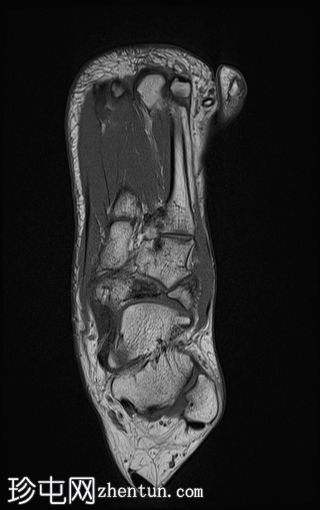

轴向PD

脂肪饱和度

舟骨呈二分状,分为两个骨块——较大的内侧骨块和较小的外侧骨块。

内侧骨折块外侧面呈“逗号状”,舟骨相对于距骨头轻微向内移位。

外侧骨折块及其外侧均呈斑片状T1低信号和PD FS高信号,并伴有硬化和微小囊肿,提示软骨联合/纤维界面存在慢性应激反应或退行性改变,可能伴有缺血性坏死。

双分舟骨区域外未见急性骨折线或骨髓水肿。

周围跗骨和关节未见明显异常。

未见明显软组织异常或关节积液。